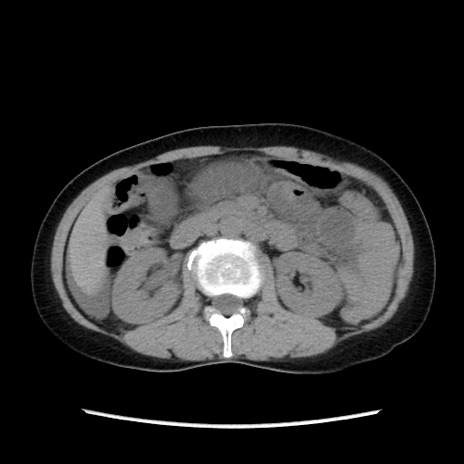

症例32(横断像)

【症例】40歳代 女性

【主訴】上腹部痛、嘔気・嘔吐

【現病歴】約9時間前頃から急に上腹部痛、嘔気、嘔吐が出現。改善しないため救急要請。

【既往歴】子宮頚癌(広汎子宮全摘術、放射線療法)、腸閉塞

【身体所見】腹部:平坦、軟、腸雑音亢進、上腹部を中心に腹部全体に圧痛あり。

【データ】WBC 8400、CRP 0.03